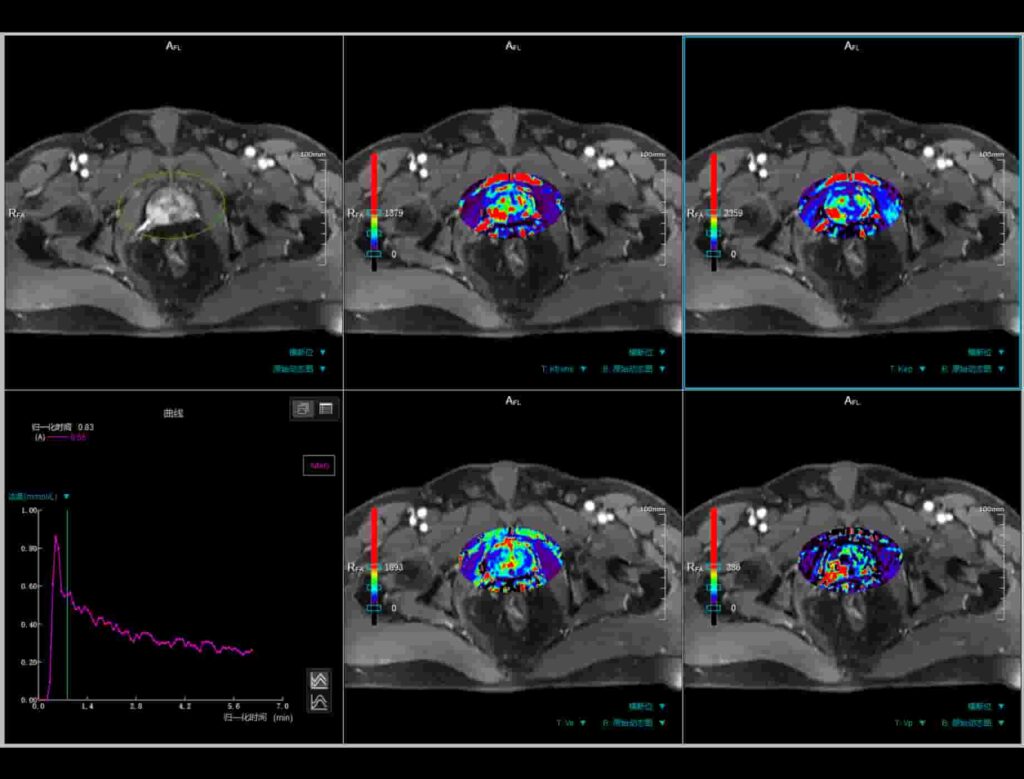

Imagerie Résonance Magnétique

Cette technologie utilisée pour réaliser des diagnostics médicaux non invasifs.

Medical Imaging Software

Les produits de Medical Imaging Software offrent des outils avancés pour visualiser, analyser et gérer efficacement les images médicales, facilitant ainsi le diagnostic et le suivi des patients.